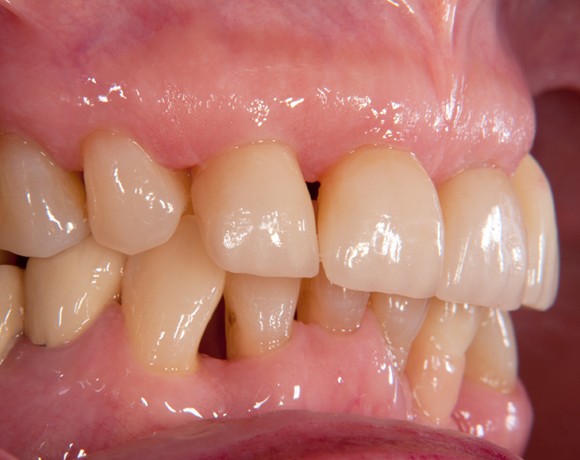

Bei dieser Patientin mussten die Zähne 22,26 und 27 aus parodontalen Gründen entfernt werden. Nach Extraktion der Zähne 22 und 26 wurden sofort in die Extraktionsalveolen die Implantate gesetzt. Zahn 27 war bereits sechs Monate zuvor extrahiert worden und die Knochenwunde gut ausgeheilt. Das geringe Knochenangebot wurde mit einem internen Sinuslift ausgeglichen. Im Bereich des Zahnes 23 wurde noch ein weiteres Implantat gesetzt. Da der Zahn 12 nicht angelegt und die Symetrie auf dieser Seite gestört war, wurden die Zähne 11 und 13 mit Teilkronen versorgt, um die Lücken zu schließen der Zahn 13 zu 12 umgebaut.